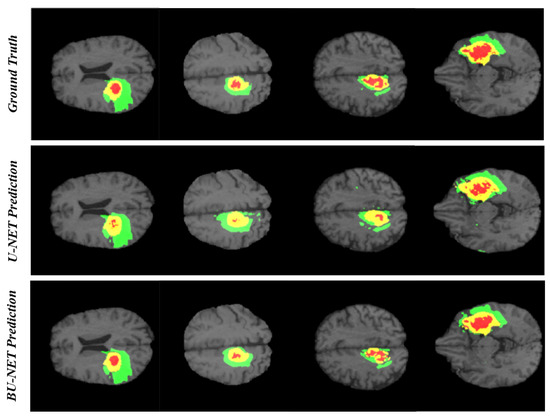

4. Results and Discussion